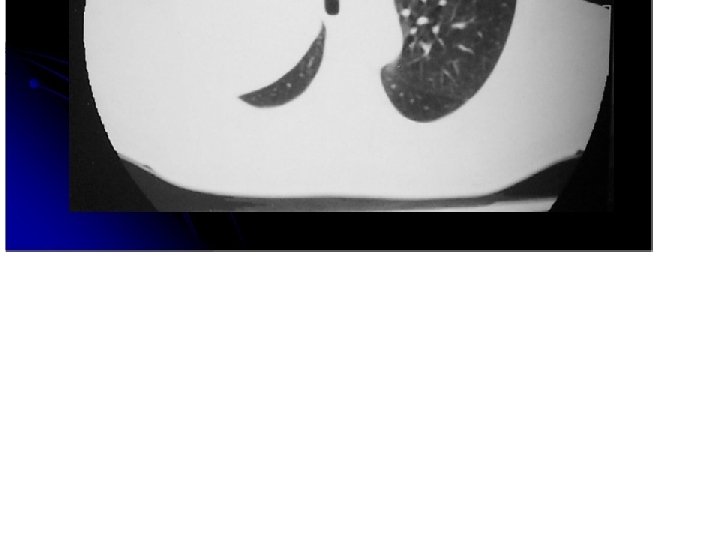

Neumonitis postobstructiva. Dilataciones bronquiales.

Nodulo pulmonar con bordes espiculados

Masa bordes lobulados y espiculados, con infiltrado intersticial.